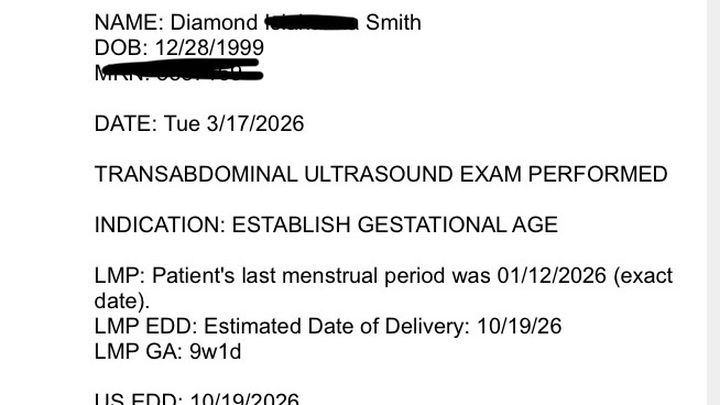

My name is Diamond. I am 26 years old and I am currently about 10 weeks pregnant as of March 23, 2026. I stay with my mom at the moment and things arent the best between us because she just recently admitted to using my credit growing up so im not able to get an apartment nor approved for a car without a cosigner cause she ruined my credit history. I called all the credit bureaus to try to unfreeze my accounts or see what I can do and seems like it’s gonna be a very long process and my due date is in October on the 19th. Not asking people to donate much, but it would be highly appreciated. If I could raise some money to get a used vehicle just for the time being so I can get him back-and-forth to work and do what I have to do to pay off what I can and be able to get a place before October or somewhere around that time. Anything would be highly appreciated. I was gonna look at some used cars on Facebook market or ask around. The lowest down payment in my area is $1200 for a decent used car and that’s honestly all that I need. The father of my child wanted to work things out then all of a sudden decided to switch up on me because he has a lot going on personally with his self which I know doesn’t sound fair, but I just want to avoid confrontation at all cause so I don’t stress.